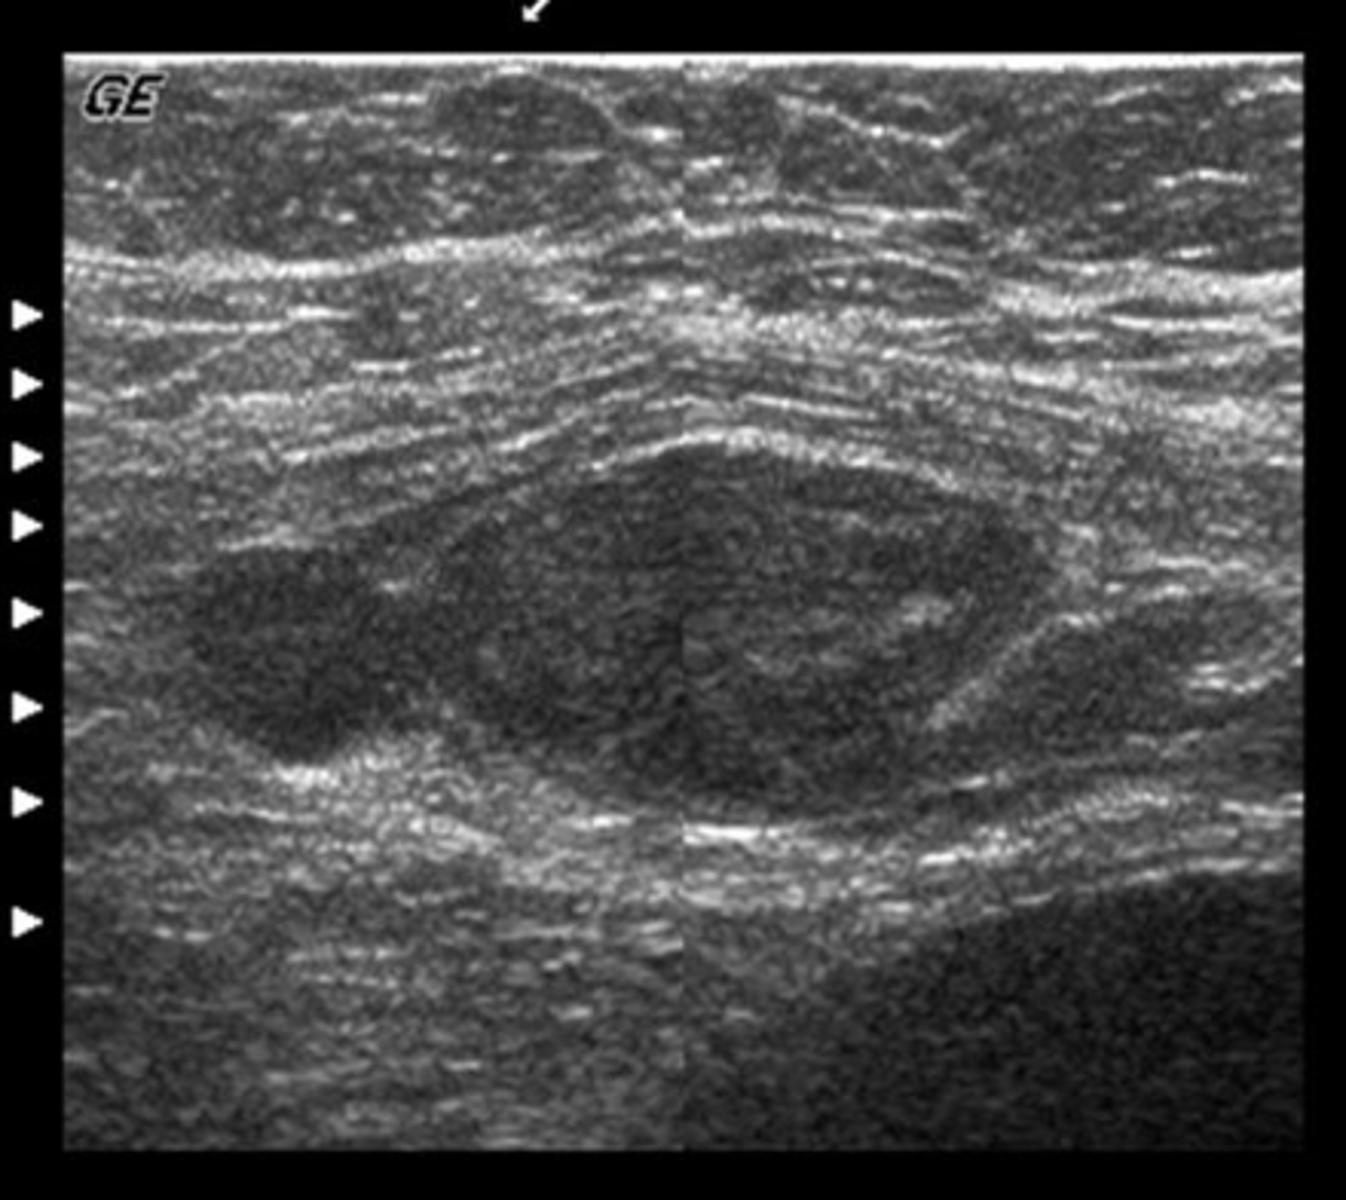

This transverse image was obtained in the mid abdomen of a 57- year-old male with lower back pain. Which of the following correctly describes the sonographic findings?

a. leaking abdominal aortic aneurysm with hematoma

b. abdominal aortic aneurysm and para-aortic lymphadenopathy

c. inflammatory abdominal aortic aneurysm

d. abdominal aortic aneurysm and horseshoe kidneys

e. abdominal aortic aneurysm with retroperitoneal fibrosis